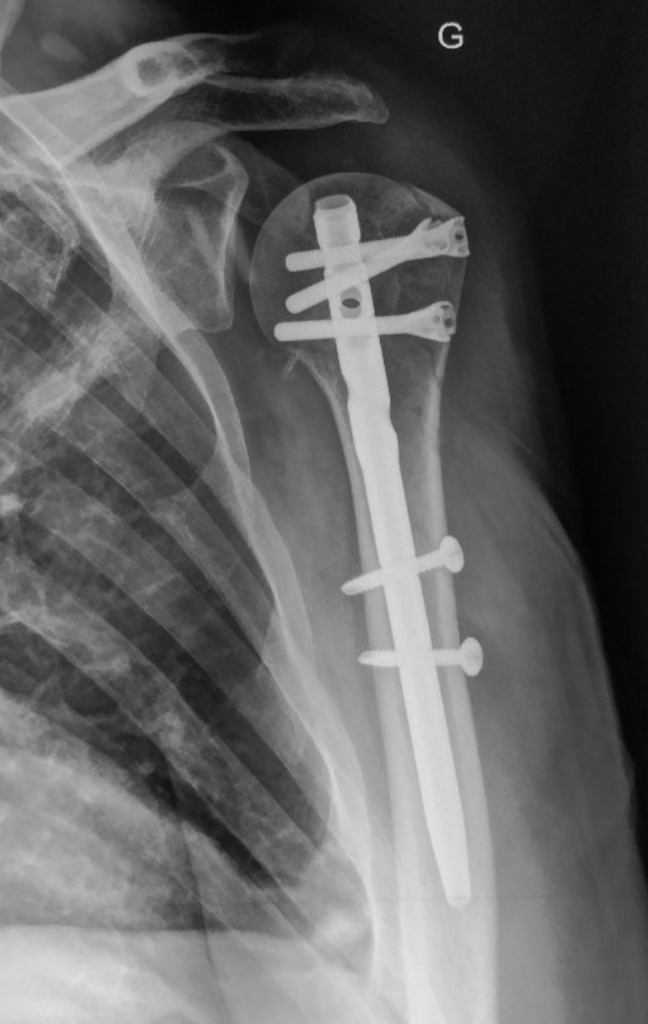

Pour les fractures plus graves, une intervention chirurgicale, telle que la fixation interne avec un matériel d’ostéosynthèse, peut être nécessaire.